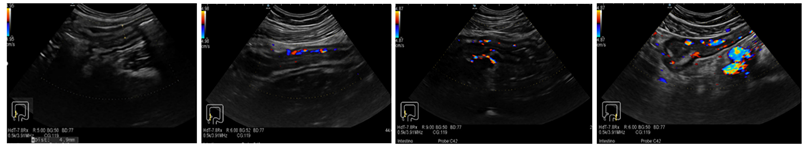

3.1. Ultrasound Features of CD